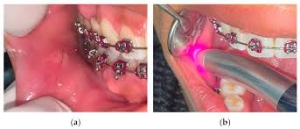

بافت متورم معمولاً در نتیجه بهداشت نامناسب دهان ایجاد می شود. این بافت اضافی نه تنها بد به نظر می رسد، بلکه روی مینای دندان نیز رشد می کند و حذف پلاک را در آینده دشوارتر می کند. به طور کلی، یک متخصص ارتودنسی ممکن است استفاده از چنین درمانی را برای ایجاد احساس راحتی بیشتر در هنگام برداشتن ساختارهای مؤثر بر دندان ها و لثه ها و همچنین خلاص شدن از شر بافت متورم، انتخاب کند که می تواند برداشتن پلاک را آسان تر کند. یکی از مواردی که استفاده از لیزر به طور چشمگیری زمان درمان را کوتاه می کند، برداشتن بافت لثه هنگام اتصال بریس است. بیماران همچنین از افزایش توانایی در حفظ بهداشت دهان و دندان سود می برند. یکی دیگر از دلایل استفاده از لیزر در ارتودنسی، برداشتن بافت متورم است. با کاهش تورم لثه ها، ارتودنتیست شما می تواند به مینای زیرین دسترسی بهتری داشته باشد و تمیز کردن کامل تر و گسترده تر را انجام دهد. بافت های متورم می توانند باعث درد شوند و به ظاهر ناسالم لثه ها کمک کنند.

روش های مرسوم برای حرکت و صاف کردن دندان ها نیاز به استفاده از بریس دارند. برای اینکه ارتودنتیست شما بتواند دندان ها را حرکت دهد، باید بتواند بریس ها را به هر کدام از دندان ها بچسباند. قبل از اینکه بتوان بریس ها را به سطح هر دندان وصل کرد، سطح باید تمیز و عاری از انسداد باشد. در برخی موارد سطح دندان توسط بافت لثه پنهان می شود. پنجمین استفاده از لیزر در ارتودنسی همانی است که در واقع زمان درمان را کوتاه می کند. با برداشتن بافت با استفاده از لیزر، می توان مدت زمان قبل از اعمال بریس را کاهش داد. مواقعی وجود دارند که سطح دندان به طور کامل یا تا حدی با بافت لثه پوشانده می شود. این ممکن است به این دلیل باشد که دندان نهفته است، یا ممکن است به این دلیل باشد که دندان کاملاً در نیامده است. اگر دندان نهفته دارید، یا دندانی دارید که تا آخر نیامده است، ممکن است نیاز به تکمیل این روش داشته باشید. به هر دلیلی، برداشتن بافت با استفاده از لیزر به منظور قرار دادن زود هنگام براکت، می تواند شش ماه تا یک سال از زمان انتظار مورد نیاز برای قرار دادن بریس ها طول بکشد. در این صورت استفاده از لیزر می تواند زمان درمان شما را به شدت کاهش دهد.